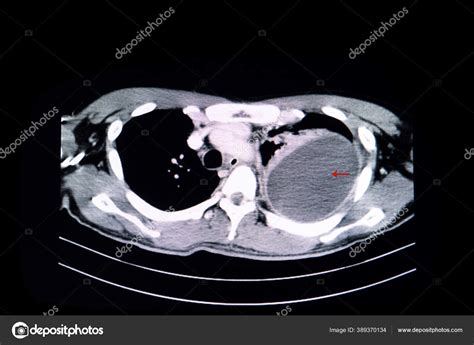

La tomografía computarizada (TAC) contrastada es la imagen de elección para la evaluación de nódulos pulmonares cavitados, ofreciendo mayor sensibilidad que la radiografía de tórax e incluso que la resonancia magnética.

Un nódulo pulmonar solitario cavitado tiene una mayor probabilidad de ser maligno. El cáncer primario de pulmón se cavita en aproximadamente el 22% de las TAC, siendo más frecuente en el carcinoma de células escamosas. Las metástasis se cavitan con menos frecuencia (menos del 4%) y suelen aparecer en las bases pulmonares y subpleurales.

Los tumores primarios suelen tener una pared interna irregular y pueden presentar señal de muesca, siendo generalmente solitarios y predominando en el lóbulo superior. Es importante considerar que lesiones de desarrollo lento como el carcinoide y el carcinoma bronquioalveolar pueden ser malignas y requerir un enfrentamiento terapéutico oportuno, incluso si su crecimiento es lento.